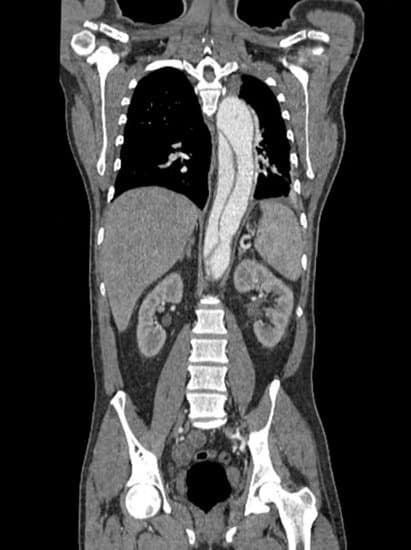

CT 혈관조영술(CT Angiography, CTA): 대동맥 상태를 가장 정확하게 평가하는 검사입니다.